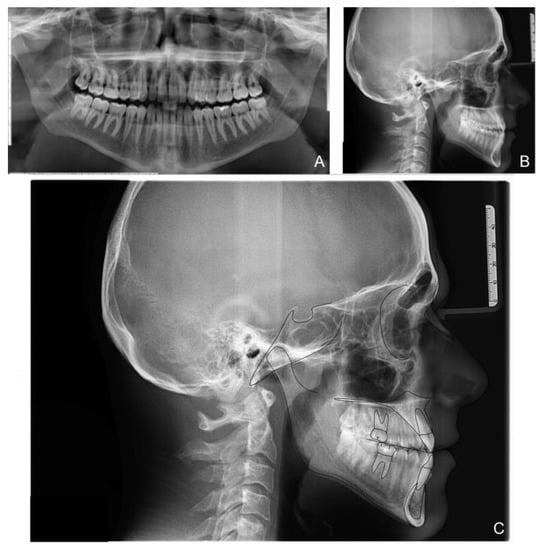

The patient correctly wore the aligners for 22 h a day with class III elastics anchored on the upper first molars and lower canines. After 12 months of treatment, the patient had improved tooth class, a positive anterior overjet, resolution of the posterior crossbite, and improved upper and lower alignment. At the end of the first phase of treatment (Figure 5), slight refinement was required. A few months later, the patient consolidated the molar and canine class I relationship, achieved a positive overjet and overbite, and resolved midline misalignment (Figure 6). At the end of the refinement phase, the patient was required to wear a long-term upper and lower Essix retention device during the night. Due to the transverse discrepancy between the upper and lower arch caused by class III malocclusion, to maintain adequate periodontal health of the upper posterior sectors, it was preferred not to expand the upper arch excessively and therefore not to resolve the crossbite of the second molars. From a cephalometric point of view (Figure 7 and Table 2), the inclination of the lower incisors and interincisal angle improved, which resulted in an aesthetic and functional enhancement. Pre-post-cephalometric evaluation, made with Deltadent® software (Outside format, Pandino, Italy), is reported in Table 3 and cephalometric tracing superimposition is shown in Figure 8.

Figure 7. Patient X-rays and cephalometry after treatment: Orthopanoramic X-ray (A); Latero-lateral skull X-ray (B); Cephalometric tracing (C).